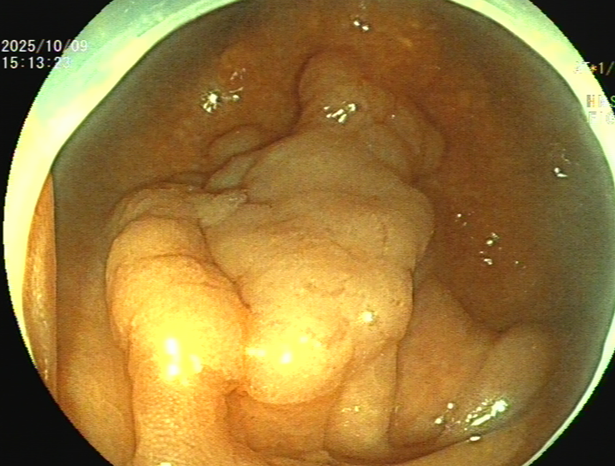

吴姨(化名)平素饮食规则,无腹痛、便血等消化道不适,因其侄女有大肠肿瘤病史,为求安心,特从外地来连州市人民医院进行肠镜检查。消化内镜室吕美光医生在检查中,凭借丰富经验和高清放大染色内镜技术,于盲肠深处发现一个与正常黏膜极其相似、范围达35mmX45mm的平坦微隆起型病灶,并确认其微表面及微血管结构存在异型。后续活检证实,该病灶为盲肠管状腺瘤。

消化内科主任潘新智与患者及家属充分沟通后,为其实施了盲肠黏膜剥离术(ESD)。术中,团队克服了盲肠病变距离肛门远,肠壁薄、蠕动频繁、随呼吸波动大等困难,以微创方法为患者完整切除了盲肠巨大侧向发育型肿瘤,避免了外科手术。

潘新智主任介绍,盲肠侧向发育型肿瘤(LST)是一种发生在盲肠部位的特殊类型的肿瘤,这种肿瘤通常呈扁平状增生,紧贴肠壁,像烙饼一样,具有比普通息肉更高的恶变潜能。由于其特殊的生长方式,盲肠侧向发育型肿瘤在内镜下治疗相对困难,耗时较长,肠道穿孔出血的风险较高,需要医生具备敏锐的观察力和丰富的经验。